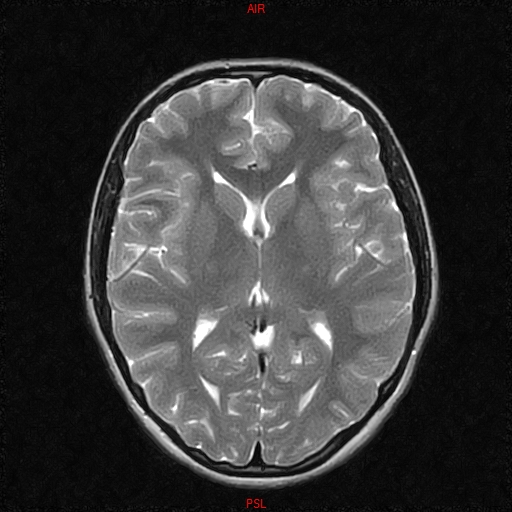

• Resonancia NORMAL CRANEAL T2 AXIAL

• Resonancia NORMAL CRANEAL T1 AXIAL